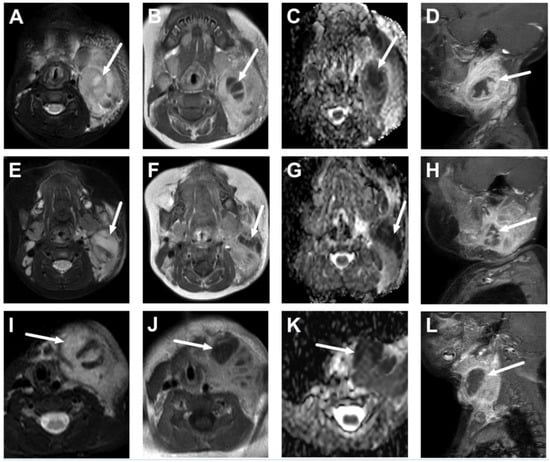

5.1. Lymphadenitis with Purulence vs. Necrosis

5.2. Cystic Masses